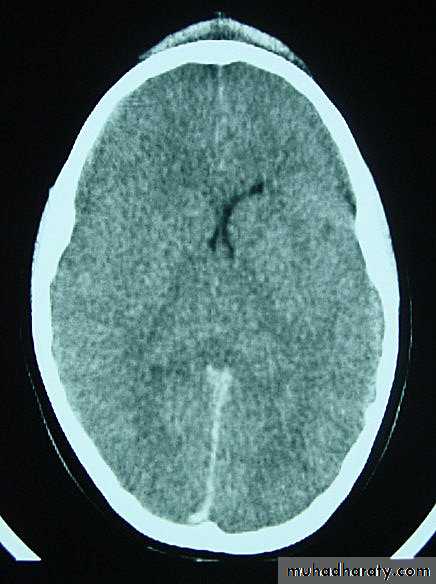

These are areas of bruising and swellings with intact pia arachnoid, localized or generalized oedema and haemorrhage due to tearing of blood vessels.3. Cerebral Contusion

Clinical presentations:1. Prolonged periods of unconsciousness.

2. Focal neurological deficits that persist for longer than 24 hours.

CT scans demonstrates contusions as small areas of haemorrhage in the cerebral parenchyma.

Contusions may resolve with the accompanying deficits or they may persist.